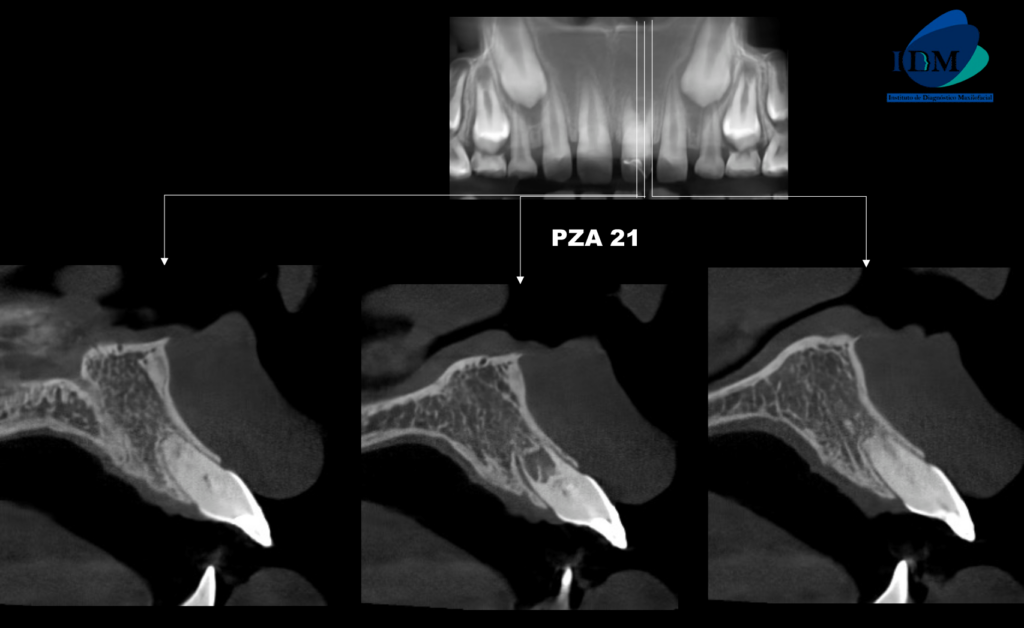

En la reconstrucción 3D se representa la obliteración del conducto y foramen apical amplio de la pieza 21 (Figura 4)

RECONSTRUCCIÓN 3D